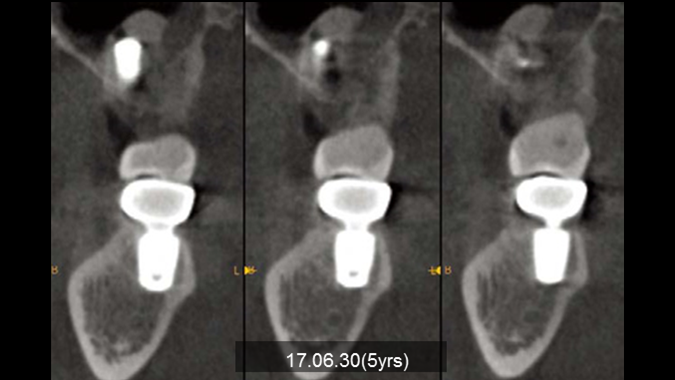

Clinical case: Bone filling into the bottom of deepest thread at 8.0mm AnyRidge fixture

- Courtesy of Dr. Kwang Bum Park -

Keywords

AnyRidge, Knifethread ,extraction socket, ,initial stability ,Allograft, ,osseointegratio ,Dr. Kwang Bum Park, , Mandibular, Single replacement, AnyRidge, Mega-oss,

Products used

Implant system-AnyRidge, Regeneration-Mega-Oss